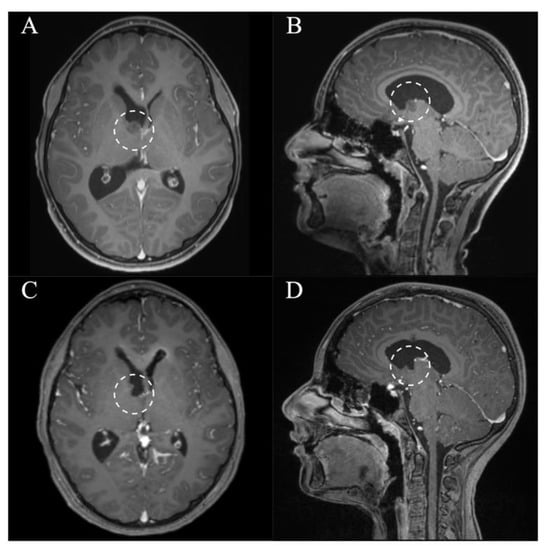

In all patients, a GTR/NTR could be achieved (Table 3). The pre- and postoperative scans of cases no. 3, 6, and 7, which were all treated through an EA approach and case no. 8, which was treated through a PE approach, are shown in Figure 3, Figure 4, Figure 5 and Figure 6. In one patient (case no. 5), due to her advanced age, we referred from resecting the vascularized capsule of the colloid cyst, achieving NTR. The mean surgery time was 163.6 ± 54.2 min (range 82–240 min) and the average blood loss was 142.5 ± 90.4 mL (range 50–300 mL). The PE approach was associated with lower mean blood loss than the EA approach (87.5 ± 47.8 mL vs. 197.5 ± 93.2 mL, p = 0.114). In four patients (50%), a total of six postoperative complications occurred, of which all were transient. Two patients (25%) showed transient cognitive impairments after resection of a colloid cyst, most likely directly associated with the endoscopic approach. The remaining four transient complications were unrelated to the use of endoscopy or NUA (Table 3). The two patients with neuropsychological evaluation showed postoperatively scores of 18/30 and 25/30 points, respectively, with a documented improvement in both patients at follow-up (18/30 to 24/30 points within 35 days and 25/30 to 30/30 points within 114 days). With regards to the remaining adult patients, no evaluation was carried out, because there was no evidence of neurocognitive deficits subjectively. In the two children with intraventricular lesions, no postoperative neurocognitive assessment was performed (due to autism disorder in the context of tuberous sclerosis in one case and due to the very young age of 5 months in the other case) (Table 3). At follow-up (15.9 ± 6.3 months; range 6.8 to 23.2 months), all patients showed improved or unchanged mRS when compared to the mRS at discharge. Complete regression or improvement of the preoperative complaints was seen in all patients, while MRI at follow-up showed no recurrence in any of the cases (Table 3).

Figure 6. Case 8. Axial and sagittal MR images, T1-weighted sequences with contrast medium preoperatively (A,B) and immediately postoperatively (C,D) after resection of a lesion originating from the right anterior thalamus via a right frontal purely endoscopic approach. It shows a gross total resection. The lesion and resection cavity is marked with a dotted circle.